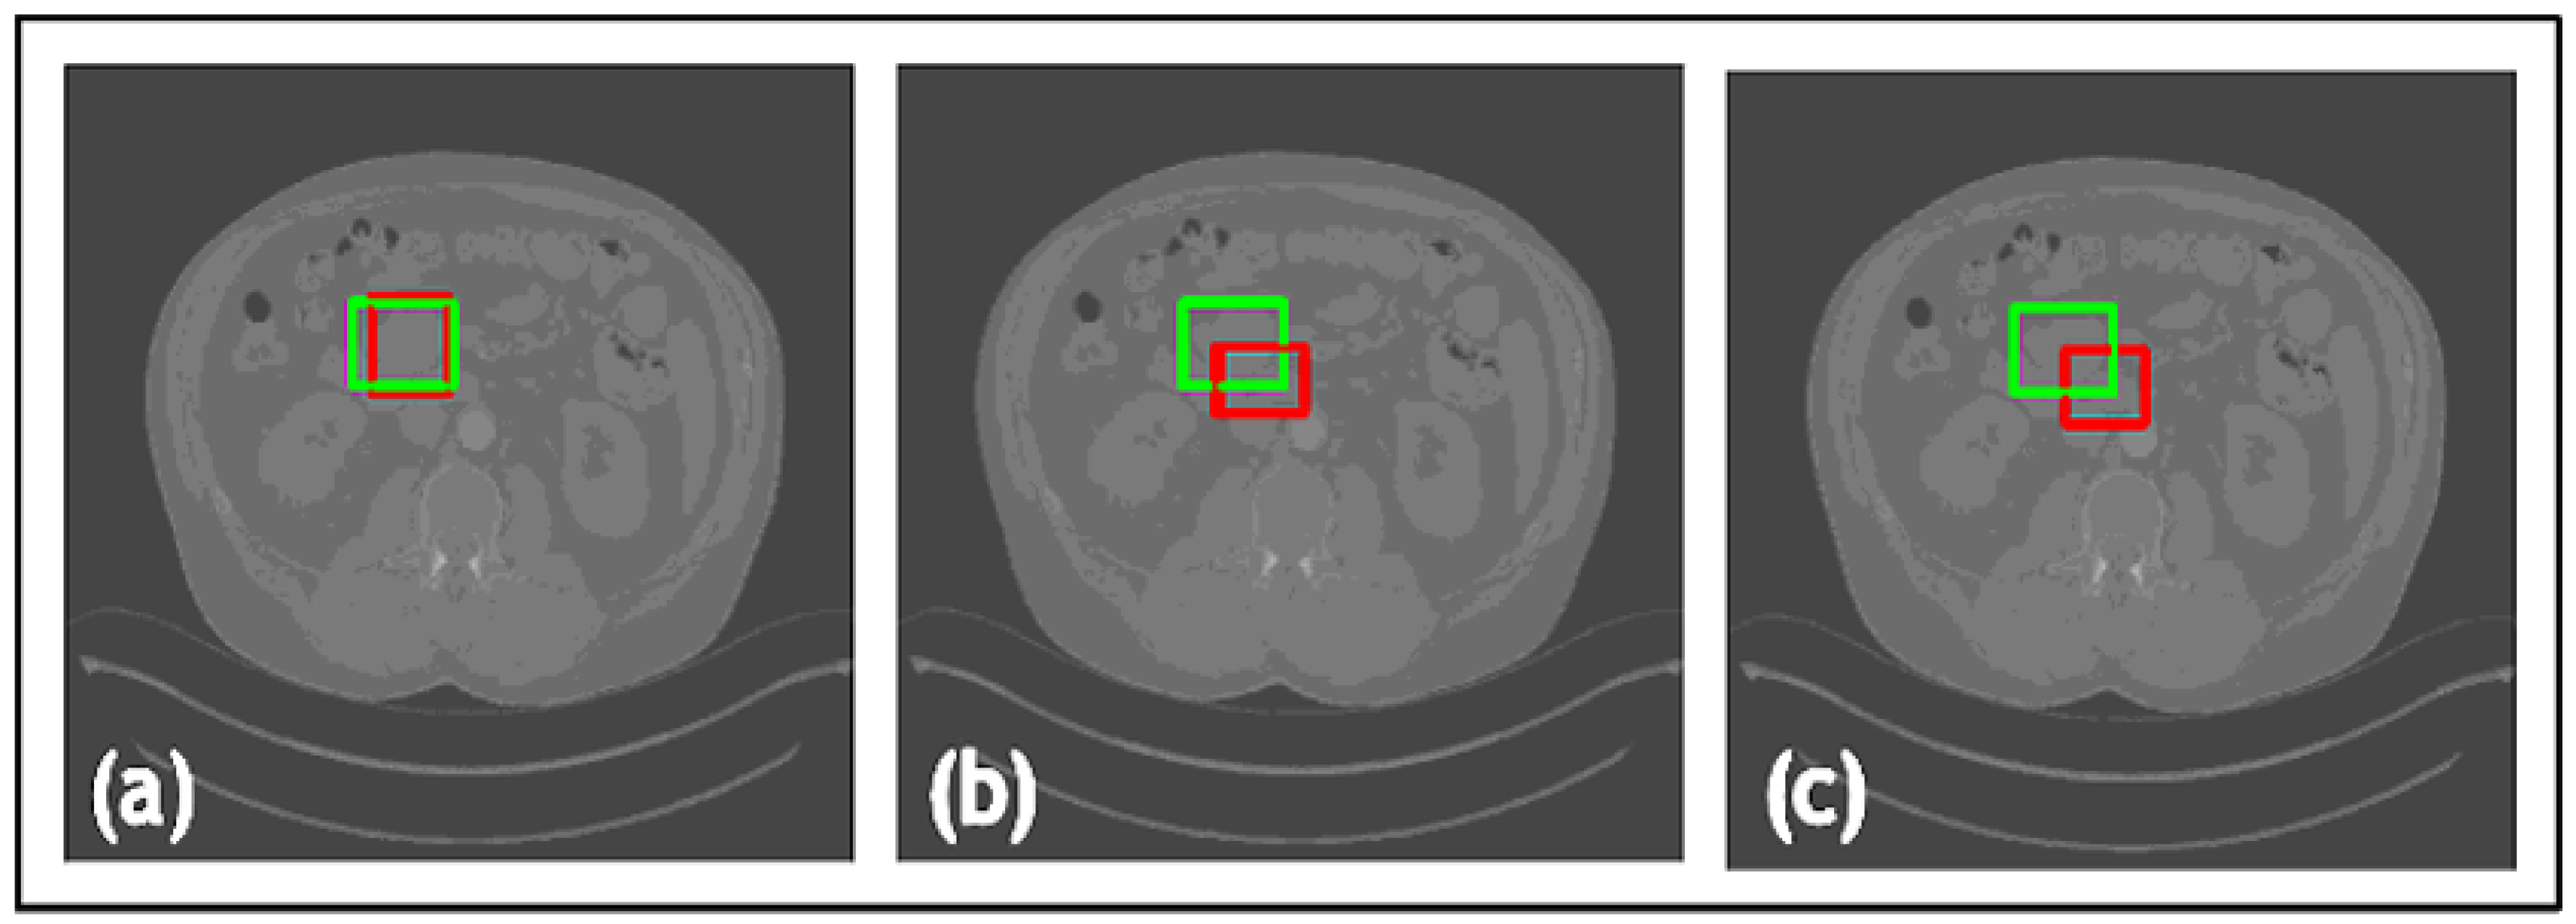

- In TED, the transformer is adapted to take in images and slide across Regions of Interest (ROIs) provided by AGs. This design aims to adaptively deal with different types of noise artifacts and thus effectively detect a variety of anomalies including tooth decay and numerous lesions across two modalities.

- A new loss function is proposed along with TED, which combines a sliding box, Intersection Over Union (IOU), and Mean Squared Error (MSE). It compares the IOU and MSE between the predicted and real bounding boxes to evaluate the regions of focus chosen by the AGs.